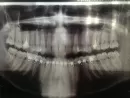

У меня стоит брекет-система на нижней челюсти с шестого по шестой зуб. Имеется скученность передних зубов. Ношу уже брекеты 11 месяцев. Зубы исправились незначительно. Зубы никакие не удаляли, т.к. врач на момент начала лечения сказал, что можно без удаления.

В настоящий момент лечащий врач говорит, что нужно удалить зубы мудрости, т.к. они не дают передним зубам выравниваться. Они у меня нормальные здоровые зубы.

Судить о клинической ситуации в полости рта исключительно по ортопантомограмме невозможно. Но, зачастую, восьмые зубы, сдавливая соседние, передают нагрузку на фронтальную группу зубов, блокируя их и не давая возможности им перемещаться.